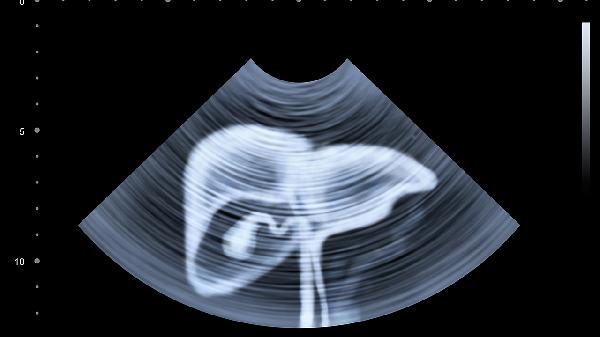

腹部四分法将腹部分为右上腹、左上腹、右下腹和左下腹四个区域,各区域包含的脏器主要有右上腹的肝脏和胆囊、左上腹的胃和脾脏、右下腹的盲肠和阑尾、左下腹的乙状结肠和部分降结肠。

右上腹主要包括肝脏和胆囊。肝脏是人体最大的实质性器官,具有代谢、解毒和分泌胆汁等功能。胆囊位于肝脏下方,负责储存和浓缩胆汁。该区域疼痛可能与肝炎、胆囊炎或胆结石等疾病有关,通常表现为右上腹隐痛或绞痛,可能伴随黄疸或消化不良。